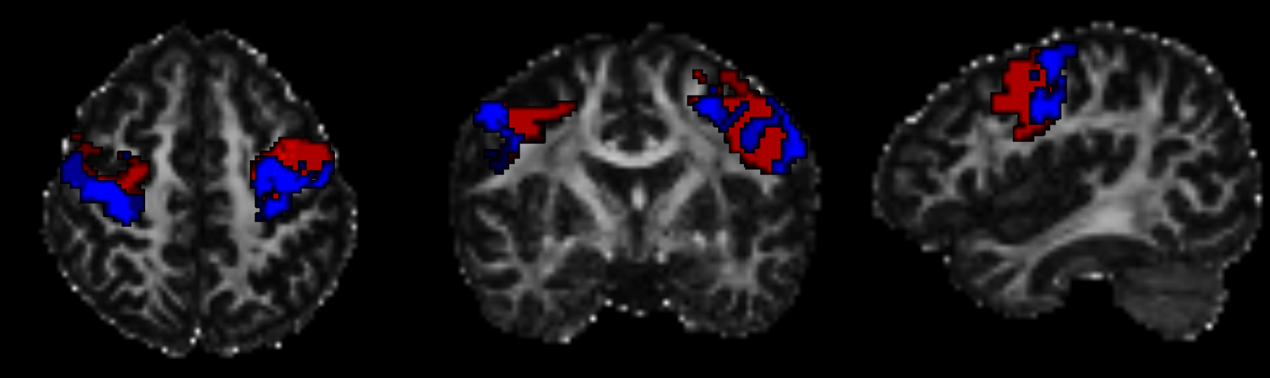

针对这一科学问题,本研究纳入34名精英篮球运动员和35名年龄、性别匹配的非运动员健康对照。在影像层面,研究基于M1与不同皮层靶区(初级感觉皮层S1、辅助运动区SMA和岛叶IA)的连接概率,采用概率纤维束追踪技术在体素水平对M1进行效应器与效应器间亚区的精准分割(见图1)。

图1初级运动皮层亚区分割示例。

(红色:效应器间亚区;蓝色:效应器亚区。)